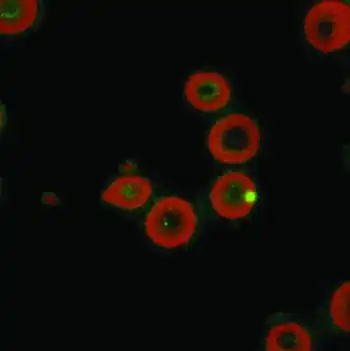

| Laser confocal microscopy shows intraerythrocytic location of Bartonella quintana[2] | |